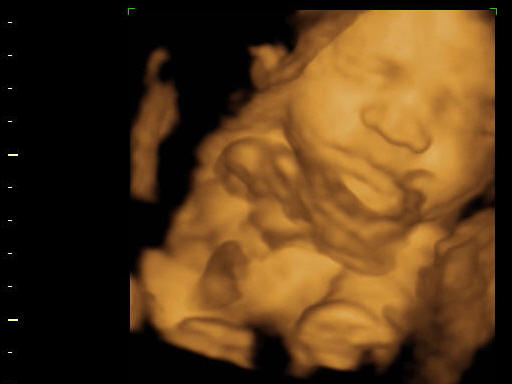

Addig is 2kép az állatkertből:

a 3d-s szemüvegben